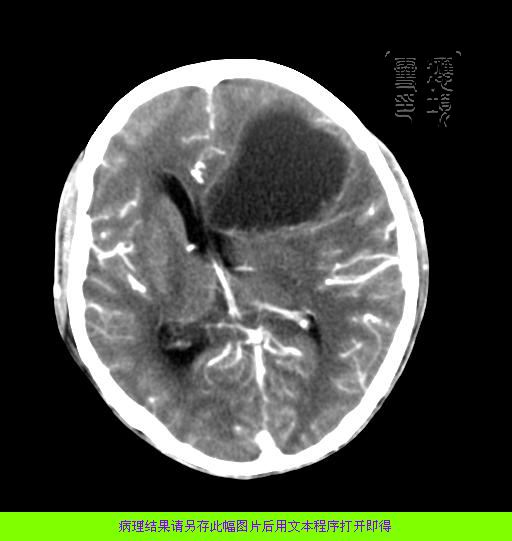

m 52y

二月前癫痫入院, 无既往史,现头痛、呕吐、视力减退、复视行ct平扫及增强检查。

见环形,结节样强化,考虑囊性星型细胞瘤。

以下是引用狙击手在2007-3-26 22:11:00的发言:[br]见环形,结节样强化,考虑囊性星型细胞瘤。

考虑囊性星型细胞瘤,ct征象大囊小结节.

左额叶囊实性占位,以囊性为主,并见明显强化不规则壁结节,占位效应明显,首先考虑是囊性星形细胞瘤.

从发病部位及年龄都不考虑是血管母细胞瘤,还有可能是胶质瘤.

胶质母细胞瘤的花边状强化及出血的特点这组片中没体现出来.还是支持囊性星型细胞瘤.